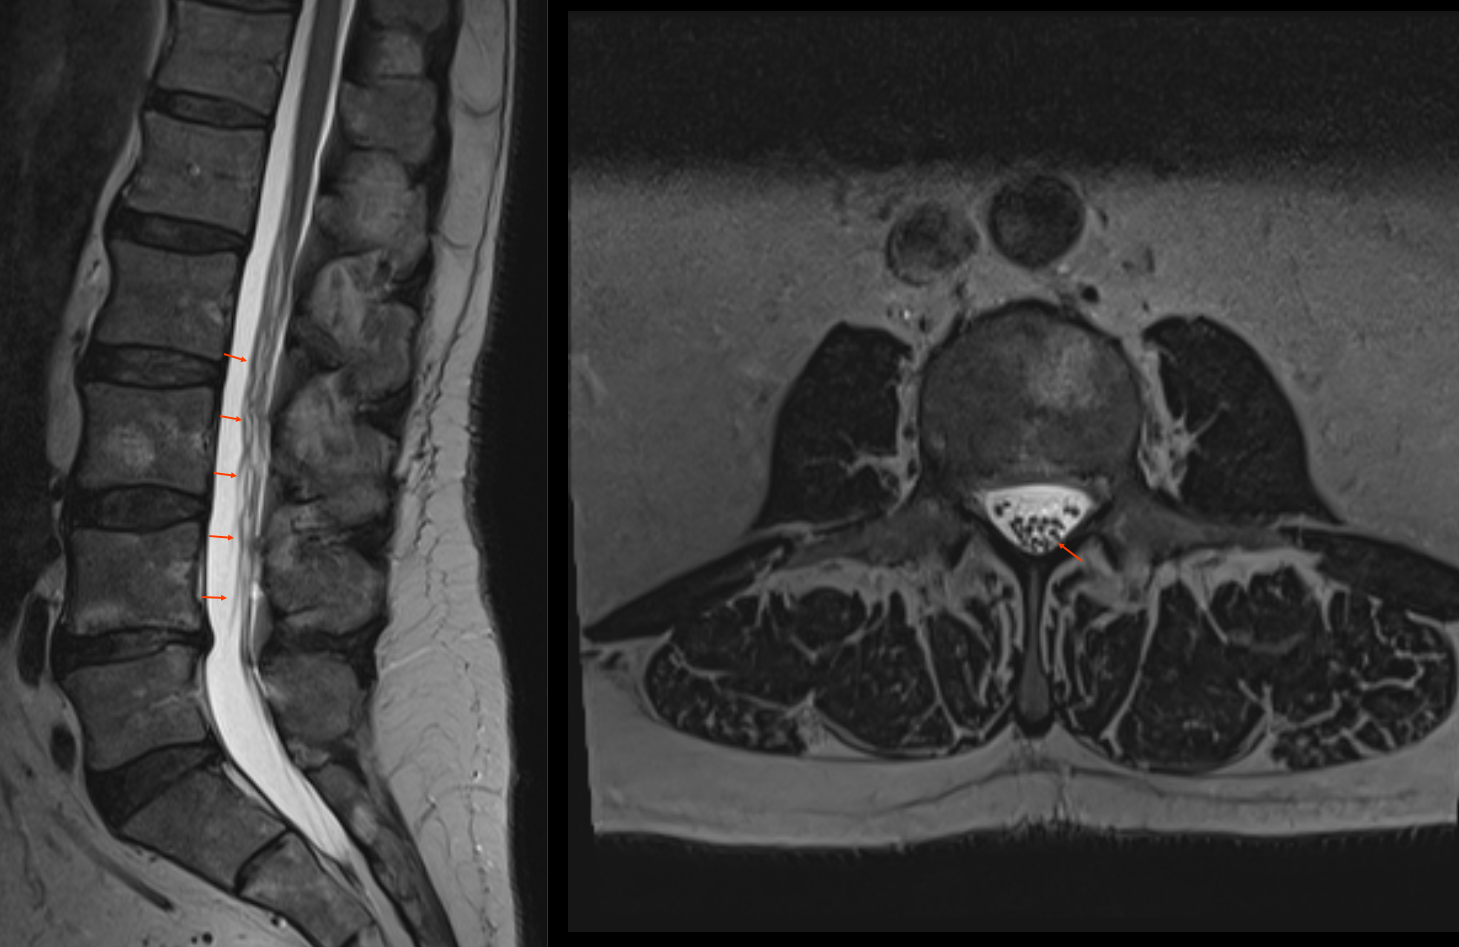

Cauda equina im MRT

Darstellung der Cauda equina im sagittalen und axialen T2 MRT Bild.